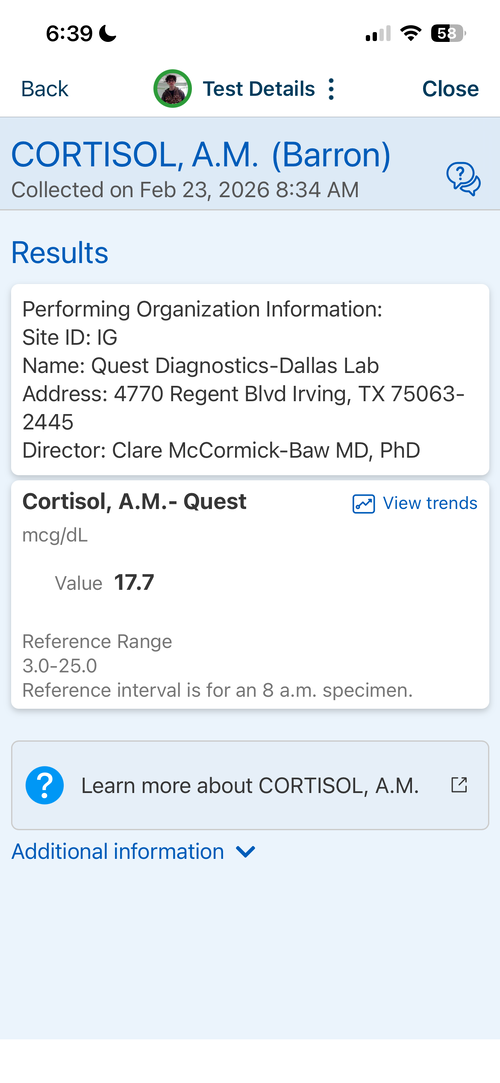

16.6 yr old male at 5'11.1" in height currently. Father is 6'1.5" and Mother is 5'8". I have images of my growth chart along with an X-Ray of my wrist attached. I also attached recent bloodwork tests of TESTOSTERONE, IGF-1 and Cortisol.